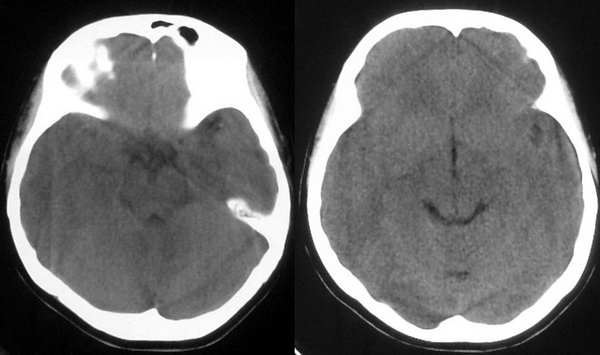

患者,女,32岁,时有头晕,无恶心呕吐。

这个病例为正常的头部ct表现,只是由于摆位不正而造成了诸多疑问,所以在工作中要注意摆位问题。

我认为是正常的颅脑影像。左侧颞顶叶脑组织示略高密度结构是近外侧裂区的正常皮质结构,不是灰质移位。由于摆的位置不正,左侧的脑组织较右侧的低一个层面。